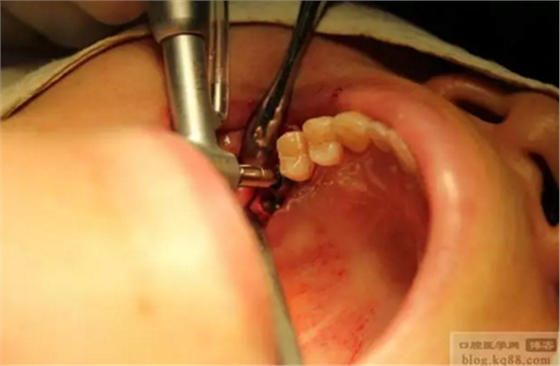

右上七可以直接看到上頜竇膜。

右上7放骨粉。

攤勻骨粉。(攤勻骨粉用的鉆頭為紅旗狀,轉(zhuǎn)速維持到20—30轉(zhuǎn))

右上6上頜竇沖頂。

右上6也植入骨粉。